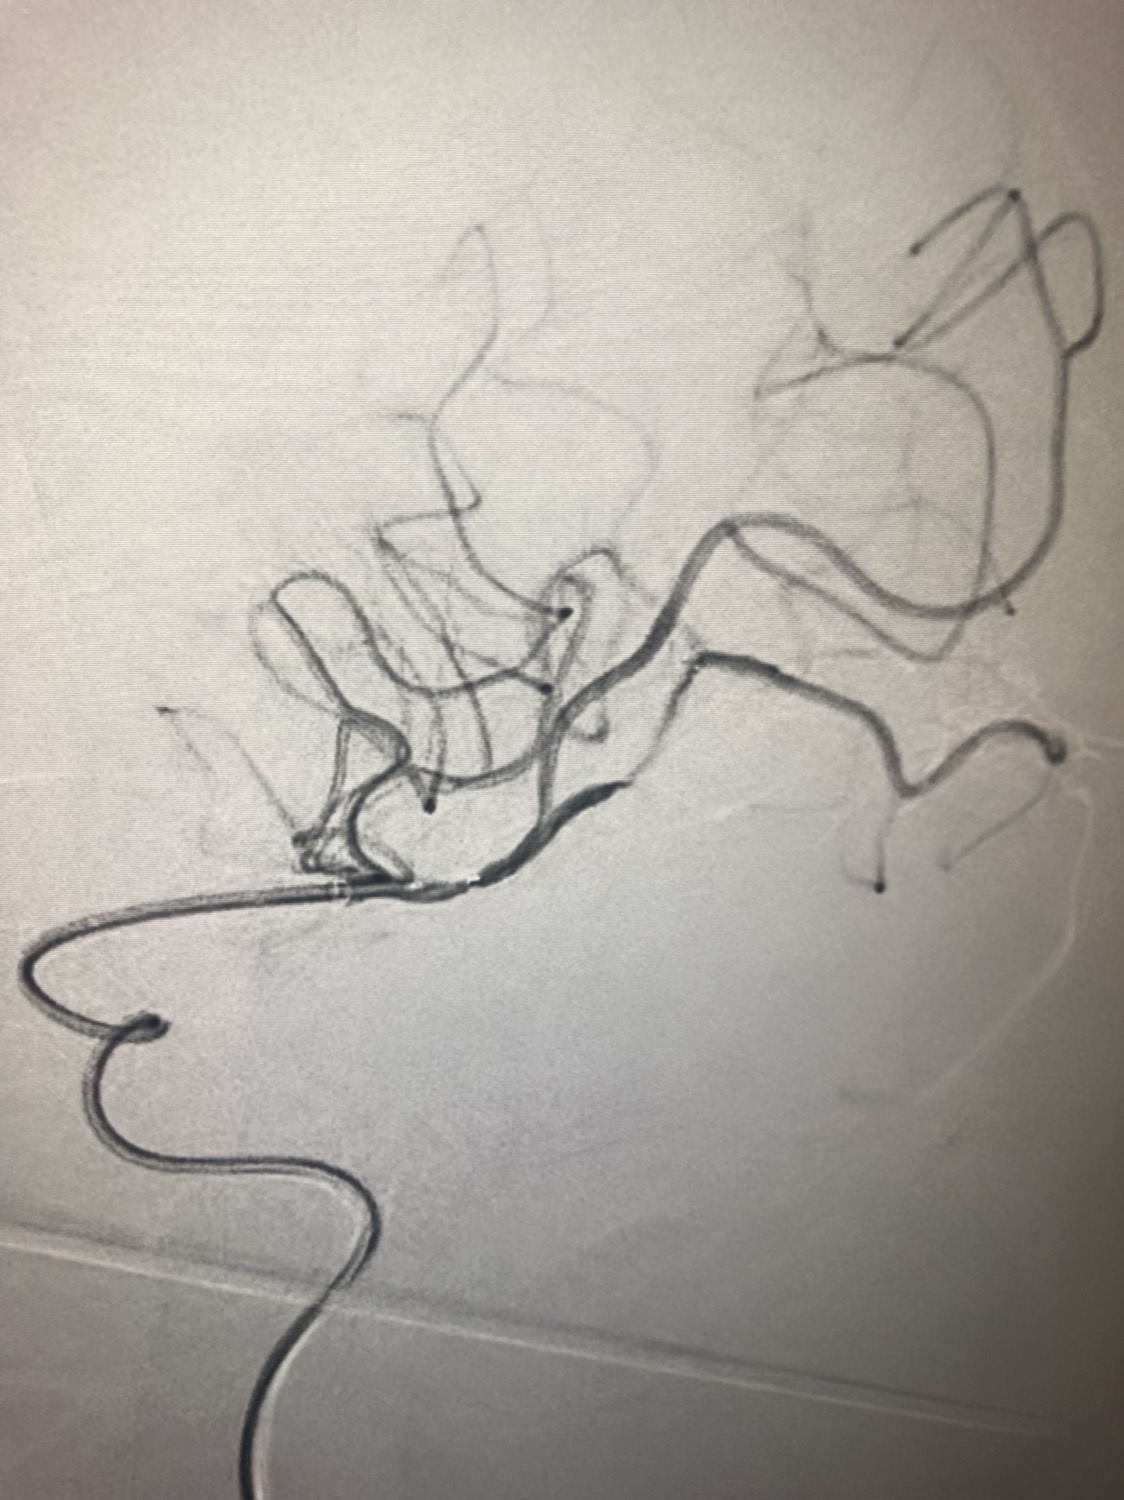

1周前房颤栓塞肱动脉,切开取栓后服用利伐沙班3天。突发偏瘫凝视3小时。上台看M3、A3血栓,国产普威森6f125cm抽吸导管高到位结合尼科3x20mm小支架,结合精细操作,m3和a3的血栓也可以轻松取出。不刺激血管。加造影射线16min两次取栓两个血管再通。

柔软的国产普威森微导管,高到位。

3x20mm的国产reco支架,适合分支血管取栓。